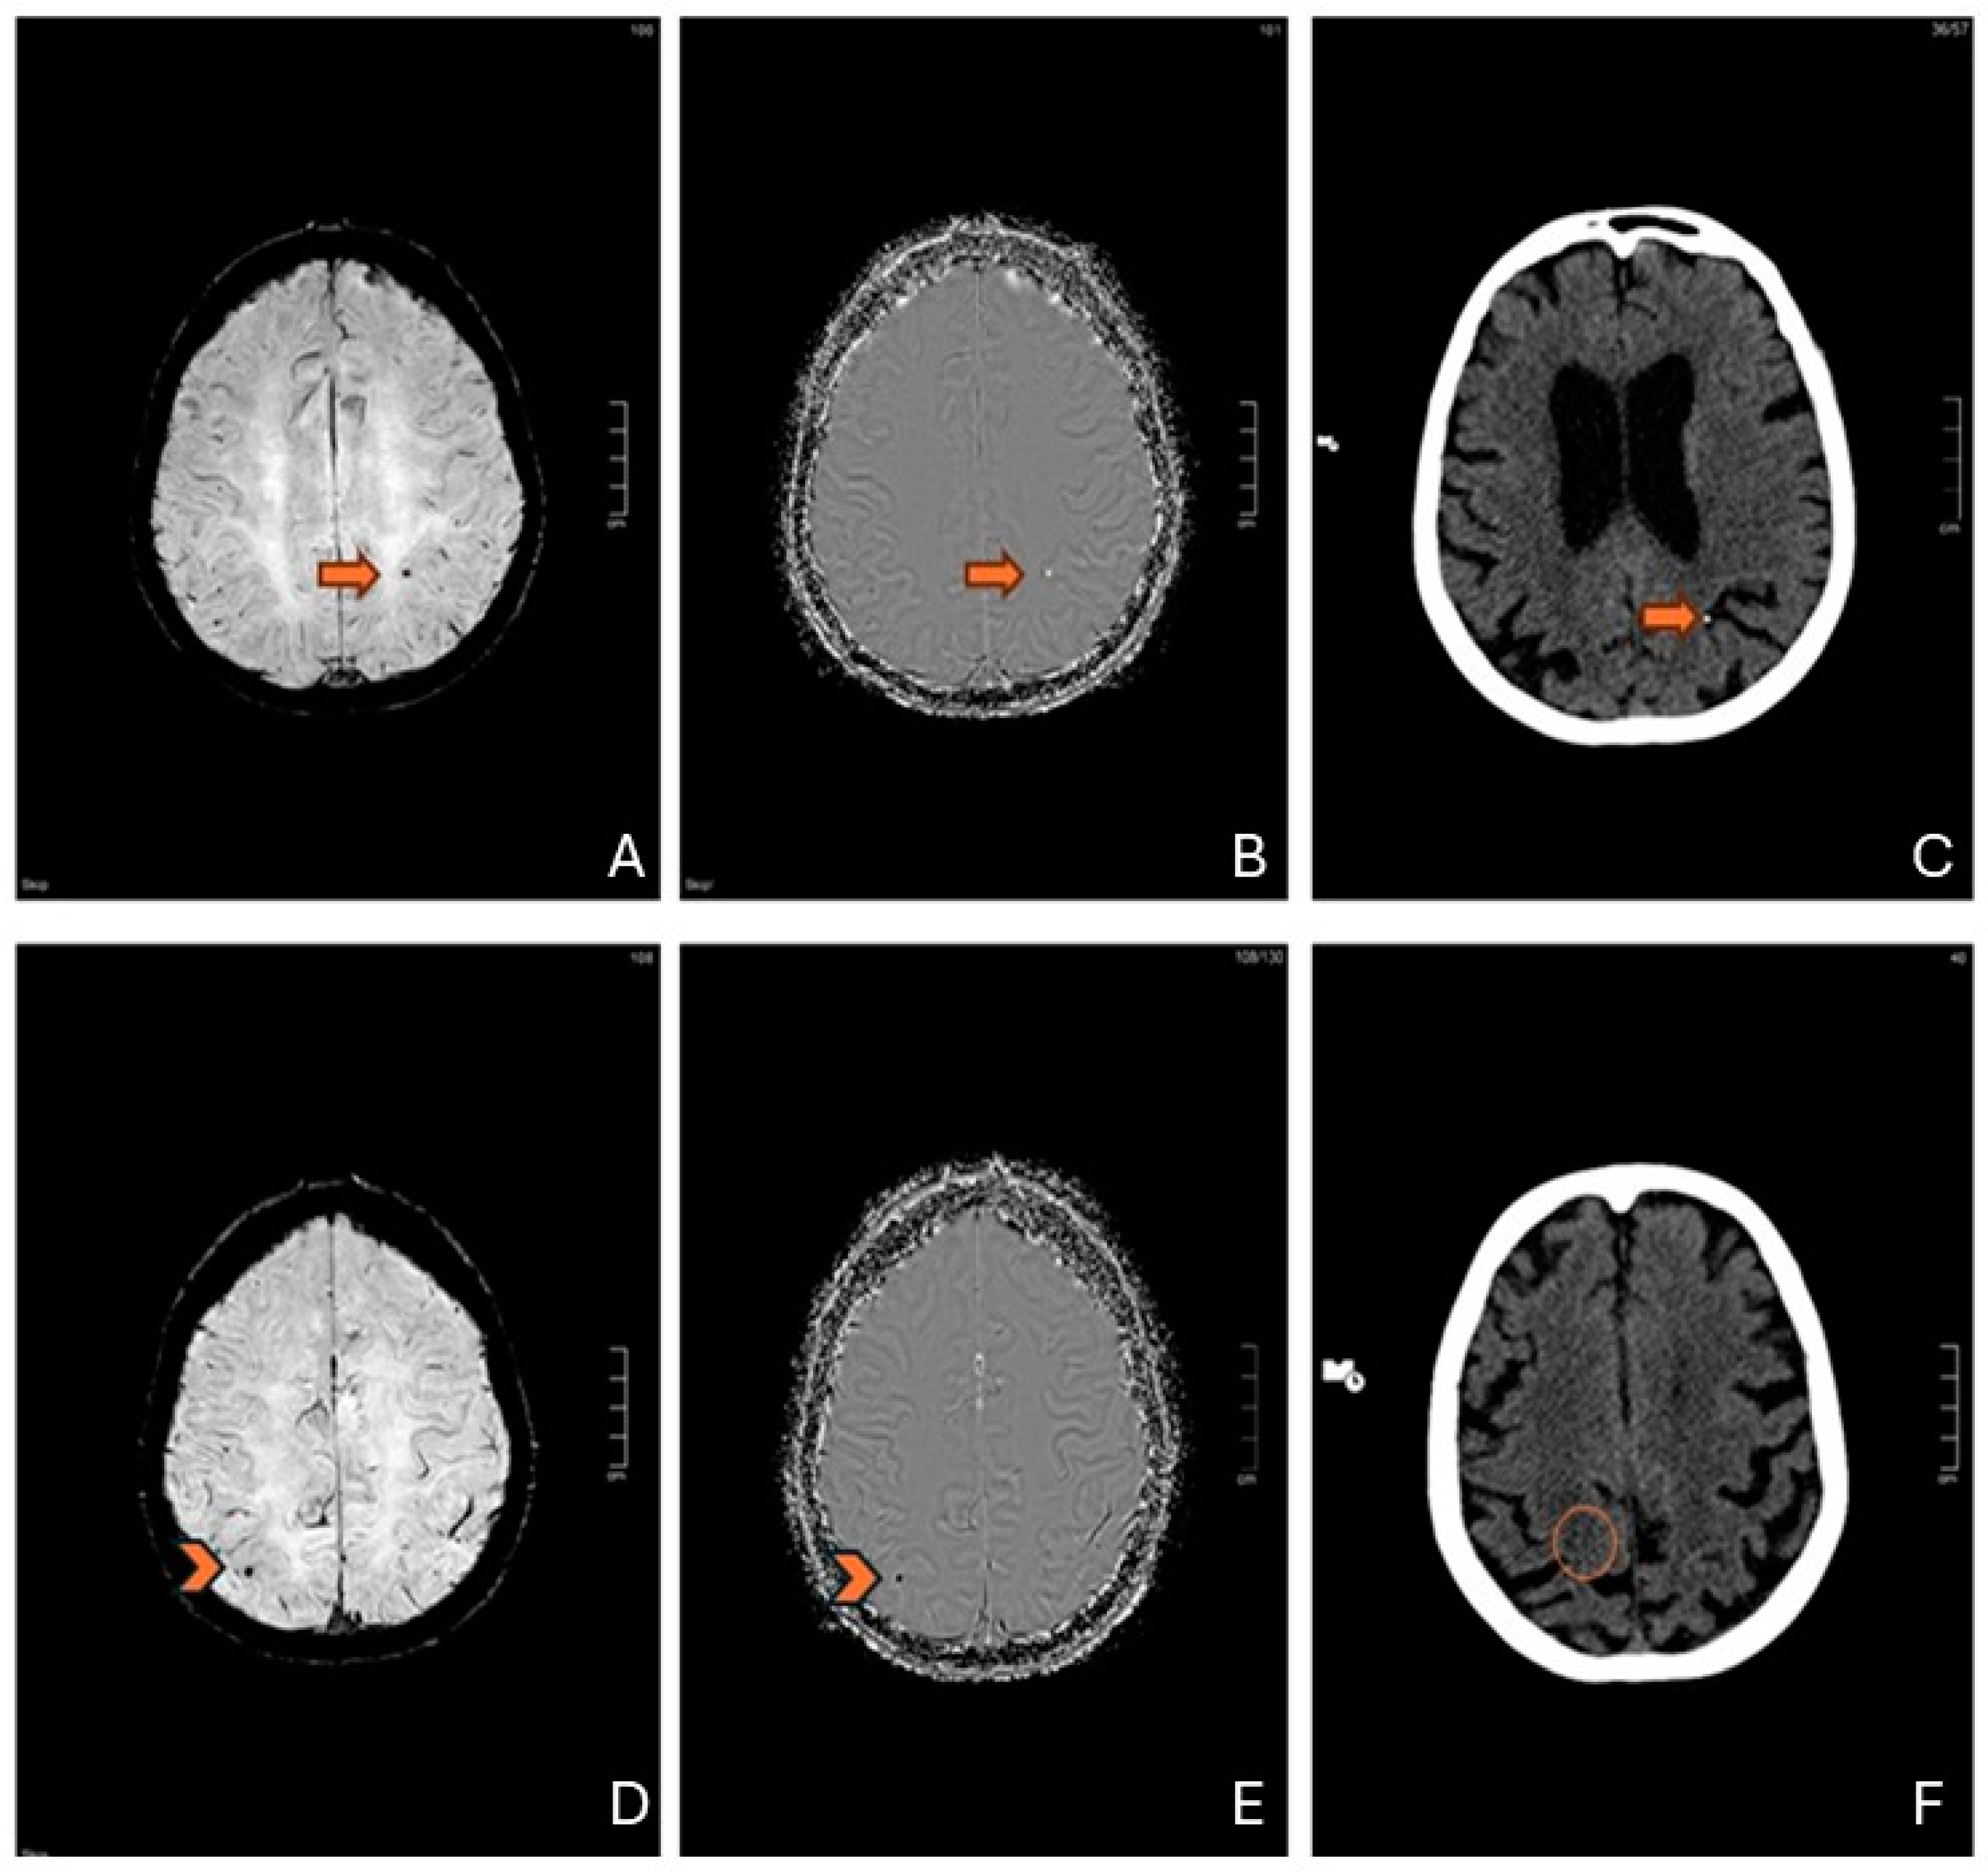

4.3. “Probable” or “Possible” CAA—Differential Diagnosis and Clinical Implications

| Differential Diagnosis | The distribution of CMBs after cardiac surgery can mimic CAA, highlighting the importance of considering this condition in the differential diagnosis. |